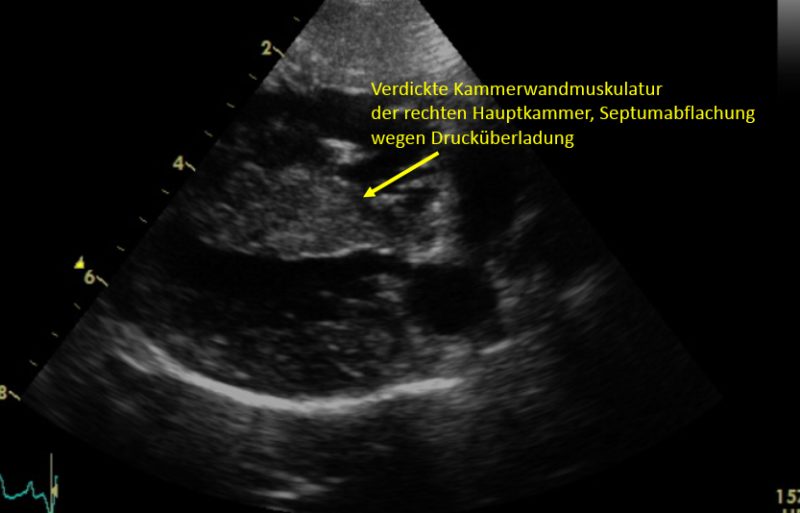

Im Herzultraschall zeigte sich eine hochgradig verdickte Muskulatur der Kammerwände der rechten Hauptkammer aufgrund einer hochgradigen Druckerhöhung. Es offenbarten sich außerdem angeborene Veränderungen der Mitralklappen und der Trikuspidalklappen. Bei der Darstellung der Pulmonalarterie zeigte sich eine missgebildete Pulmonalklappe, die wenig beweglich war. Zudem schloss und öffnete sie sich nicht vollständig. Die hochgradige Verwachsung der Pulmonalklappenöffnung führte zu einem sehr starken Anstieg des Blutdrucks von normalerweise 20 mmHg (Millimeter Quecksilbersäule) auf über 200 in der rechten Hauptkammer. Außerdem war der Klappenring der Pulmonalarterie sehr eng angelegt, wodurch der Schweregrad zusätzlich negativ beeinflusst wurde.

Je höher der Druck in der rechten Kammer ist, desto hochgradiger wird die Verdickung der Muskulatur im rechten Herzen. Symptome können Schwäche, Synkopen (Ohnmachtsanfälle) oder ein Rechtsherzversagen sein (wie im Falle von Gonzo, der dadurch eine hochgradige Bauchwassersucht entwickelte). Während leicht bis mittelgradig betroffene Patienten eine normale Lebenserwartung haben, erwartet hochgradige Patienten ohne Eingriff in der Regel ein vorzeitiges Ableben. Dabei zählt bereits ein Druckgradient von 80mmHg als hochgradig. Gonzo hatte anfangs einen Druckgradienten von über 200 mmHg! Eine Absenkung durch den Eingriff auf 75 mmHg spricht für einen absolut erfolgreichen Eingriff.